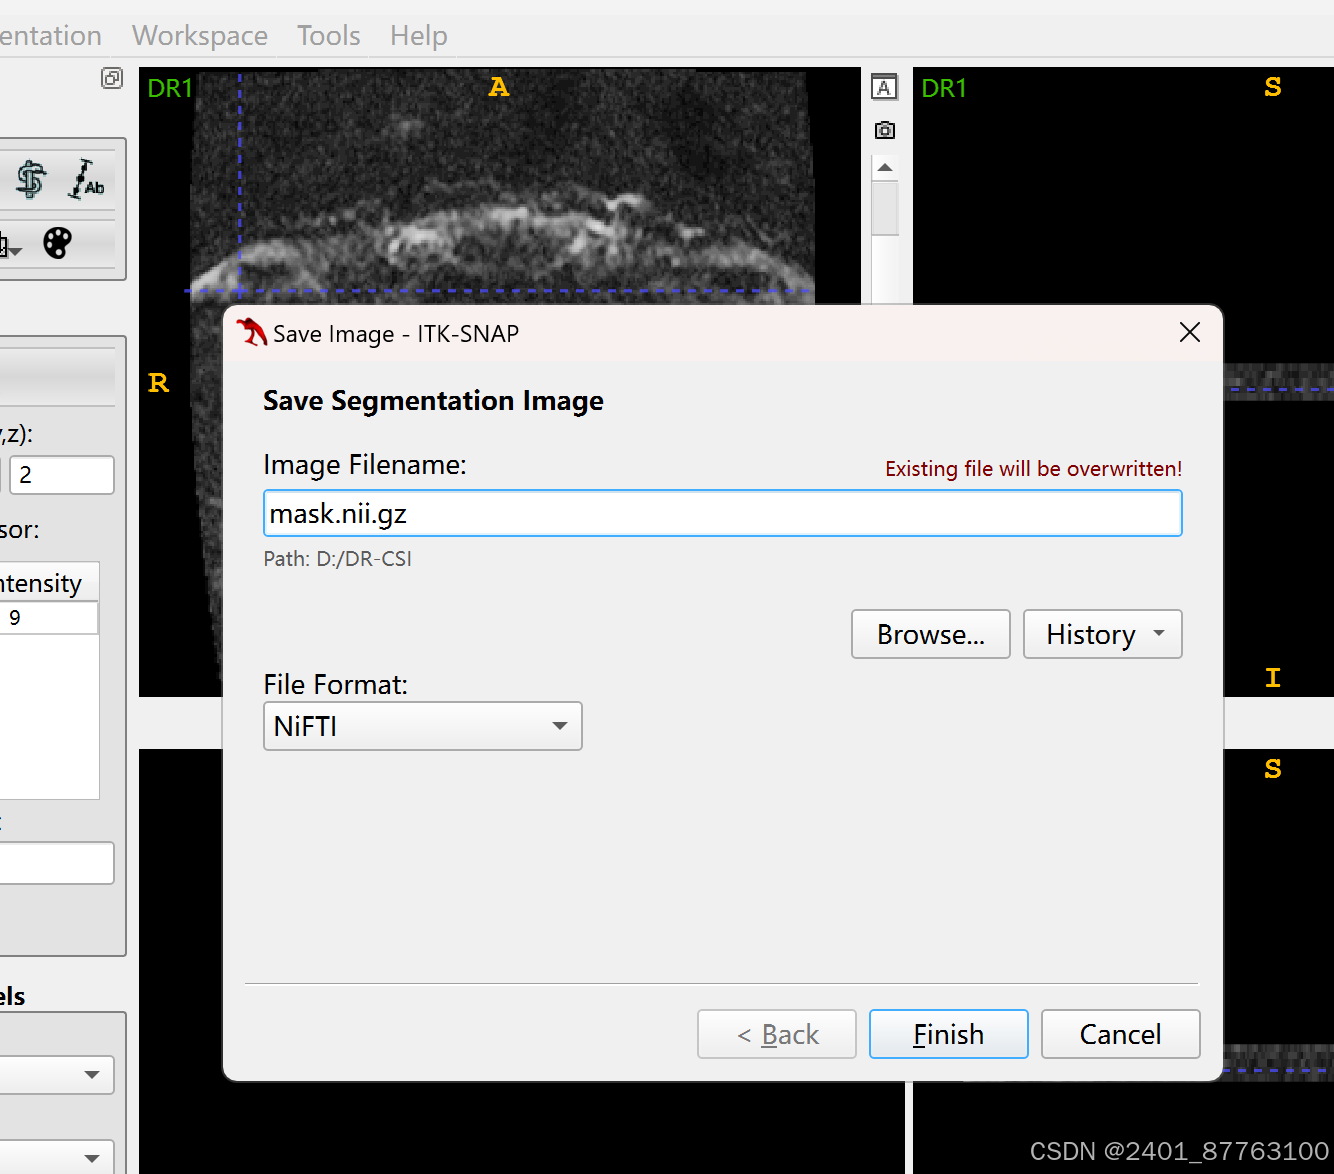

勾好后点击segmentation--save segmentation image

自己保存路径。